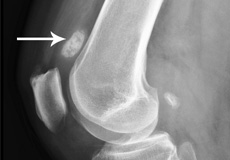

Osteonecrosis of the Knee

Osteonecrosis is a condition in which the death of a section of bone occurs because of lack of blood supply to it. It is one of the most common causes of knee pain in older women. Women over 60 years of age are commonly affected, three times more often than men.